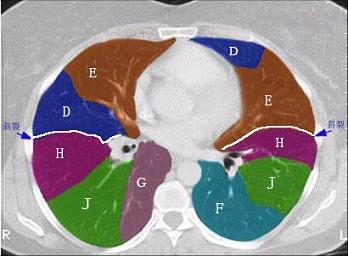

结合肺段模式心室层面(见图),选出右肺上叶的组成 ( )A、A+B+C+DB、A+B+C+D+EC、A+BD、A+B+CE、A

问题 结合肺段模式心室层面(见图),选出右肺上叶的组成 ( )

选项 A、A+B+C+D B、A+B+C+D+E C、A+B D、A+B+C E、A

答案 D